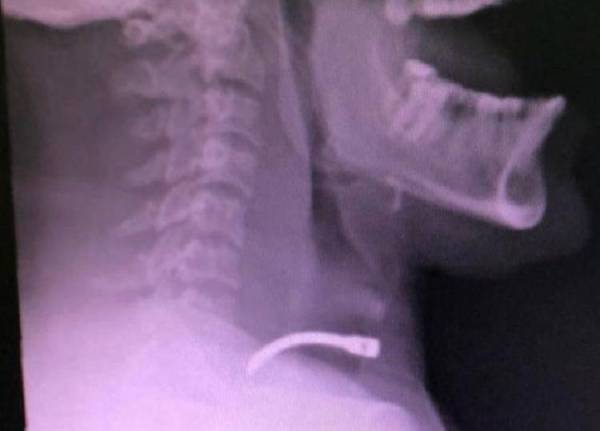

أنقذت مدينة الملك سعود الطبية ممثلة بمركز الإصابات والحوادث، مقيماً تعرض لإصابة نافذة في الرقبة من مسدس طلقات للمسامير أثناء مزاولة مهنته.

وأوضحت المدينة الطبية أن الإصابة نتج عنها تهتك في الشريان السباتي الأيمن، وتم نقل المريض إلى غرفة العمليات، والتحكم في النزيف وإصلاح الشريان، ثم نُقِلَ المريض إلى قسم الإفاقة، ومنه إلى قسم المراقبة بجناح مرضى الإصابات.